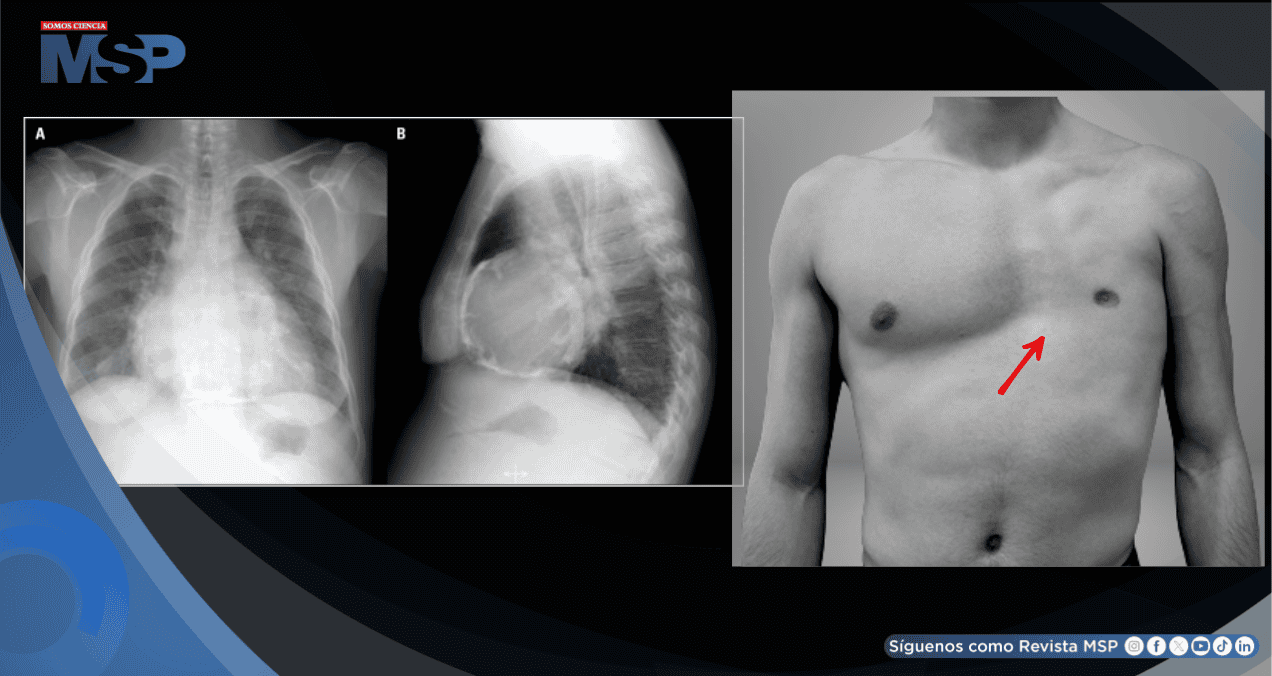

Sus antecedentes personales destacaban por la presencia de anomalías congénitas, incluyendo una asimetría notable en la pared torácica, braquidactilia (dedos cortos) y sindactilia (dedos unidos parcial o totalmente), aunque nunca había recibido un diagnóstico formal de síndrome de Poland.

Sin embargo, la TC confirmó la sospecha clínica de una anomalía congénita al observar una marcada asimetría en la musculatura de la pared torácica, con ausencia completa de los músculos pectoral mayor y menor en el lado izquierdo a la altura del esternón, un hallazgo característico del síndrome de Poland.

Simultáneamente, la confirmación por imagen de la ausencia congénita de los músculos pectorales permitió diagnosticar formalmente el síndrome de Poland. Por lo tanto, el diagnóstico final fue: Síndrome de Poland con pericarditis aguda de probable etiología idiopática (sin causa infecciosa, autoinmune o traumática identificada).